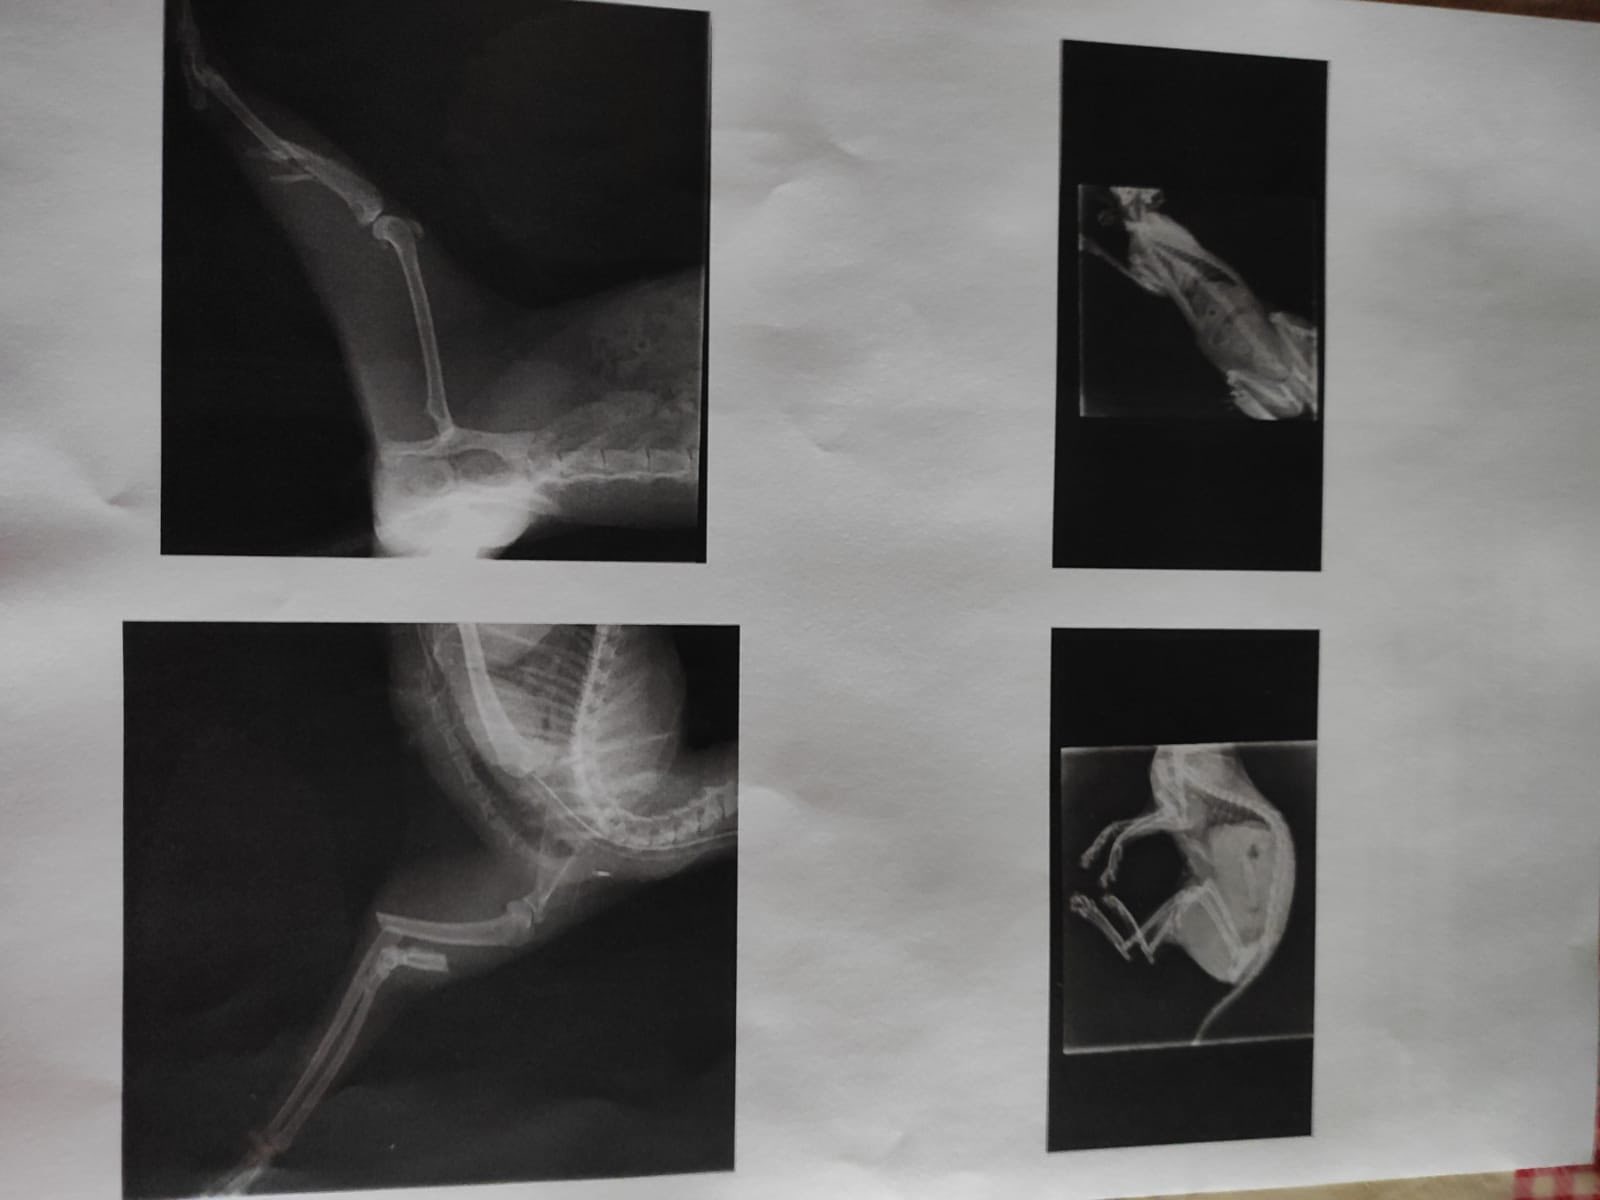

Avril 2025

PARRAINAGE CLOS, MERCI POUR VOTRE GENEROSITE POUR CETTE PETITE MINETTE!

PARRAINAGE POUR SYMPHONIE